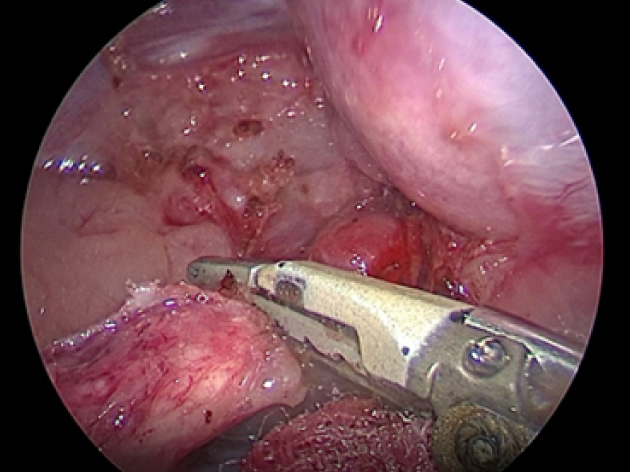

副腎の周りを完全に剥離したら超音波メスで離断していきます。

実際の手術風景です。

犬の右副腎2.5cm。腹腔鏡下手術。3ポートで摘出が可能。

CLARA&CROMAという新しいモードで手術している。

これは暗いところ明るくし、CROMAは赤を強くしコントラストをつけることにより血管一本までしっかりと確認することができる。

少しギラギラするが、手術しやすくなる。